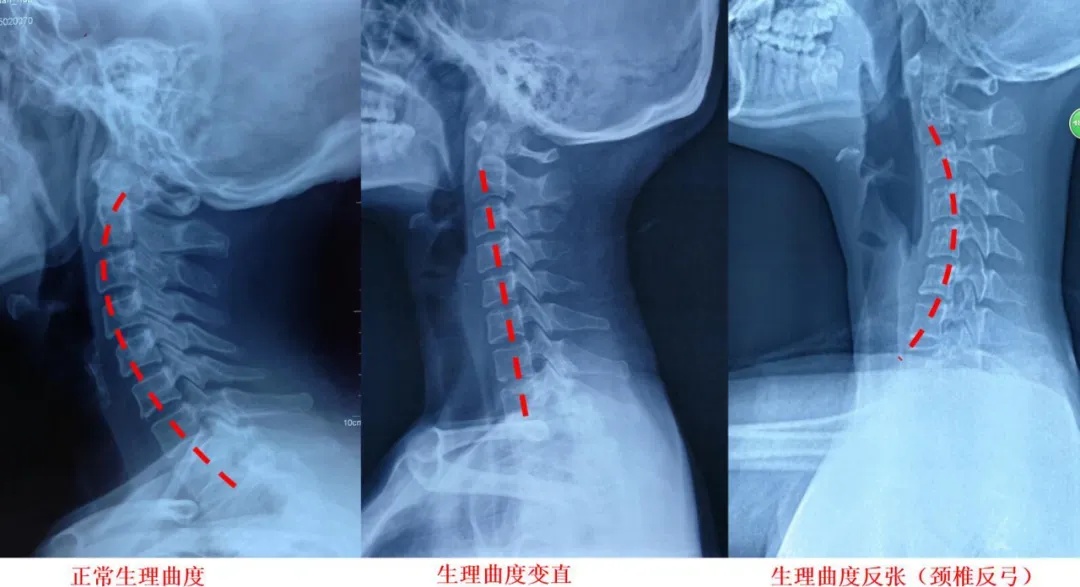

什么是颈椎反弓?

正常颈椎曲度生理性前凸,它既保证了颈椎活动的高度灵活性,又减轻了颈椎间盘的重力负荷,使颈椎处于最佳的力线状态下工作。

如果没有生理弯曲,颈椎会出现僵直,甚至向相反的方向弯曲,就称为颈椎反弓。